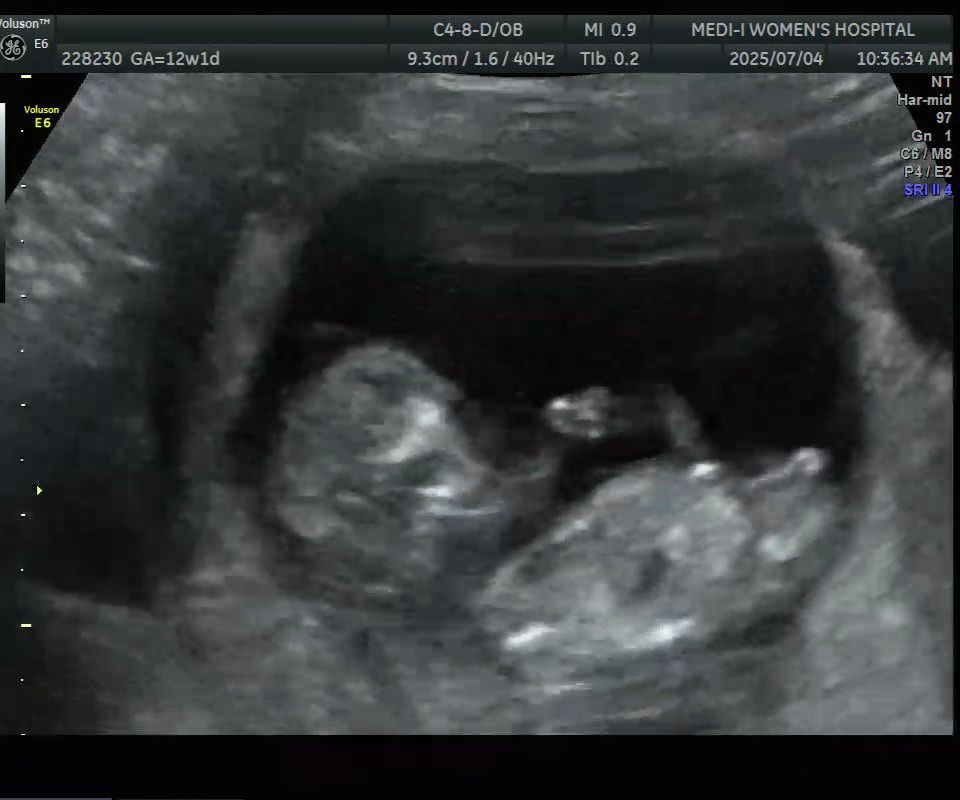

12주 각도법 봐주실수 있나요? 궁금해서 잠을 못잤습니다 ㅎ

딸인것 같은데 맞을까요?

생식기끝에 갈고리 모양 아들이요

왕자님에 한표요